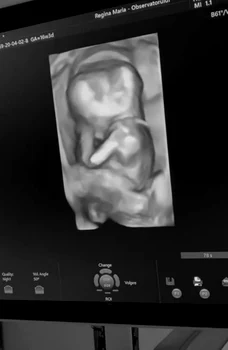

După emisiune, se pare că Alina Ceuşan şi Raul Tişa au hotărât să devină părinţi. Iată că acum, deodată, Alina Ceuşan dezvăluie că este însărcinată. Luni de zile a ascuns burtica care se vede foarte bine, semn că a trecut de primul trimestru de sarcină. Într-un video emoţionant postat pe reţelele de socializare, Alina povesteşte fiecare moment, fiecare vizită la medic, fiecare reacţie.

În imagini se poate observa că vedeta se simte foarte bine, sarcina decurge normal, aceasta făcând vizite regulate la medic. Se pare că în septembrie, Alina Ceuşan va naşte primul copil.